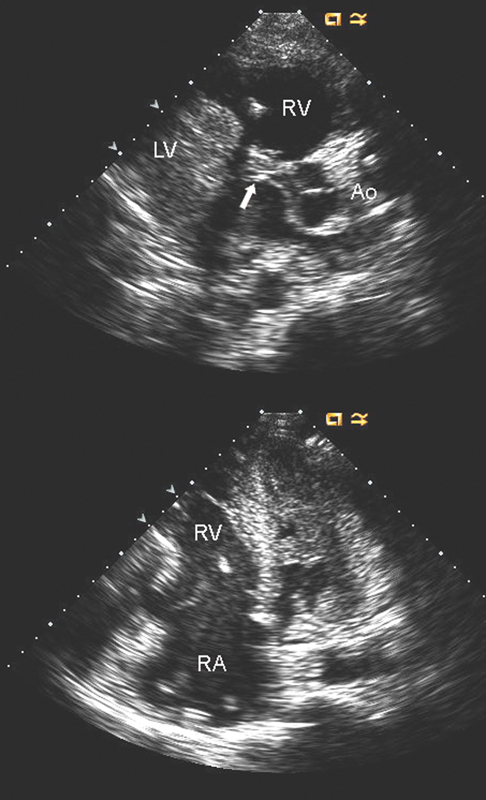

فحوصات تشخيصية لبعض امراض القلب والشرايين التاجية